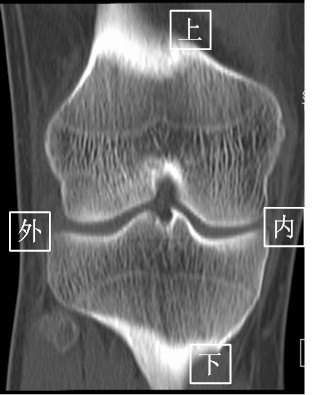

2.CT(以膝关节为例)

由于CT 是三维成像,包括矢状面,冠状面和横断面三个层面的扫描。一张CT片子也是包括医院、姓名、性别、年龄、检查日期、侧别、扫描序列等信息的。

矢状面---是从前向后、从内往外扫描成像。

冠状面---是从内向外、从前往后扫描成像。

横断面---是从上向下、从前往后扫描成像。